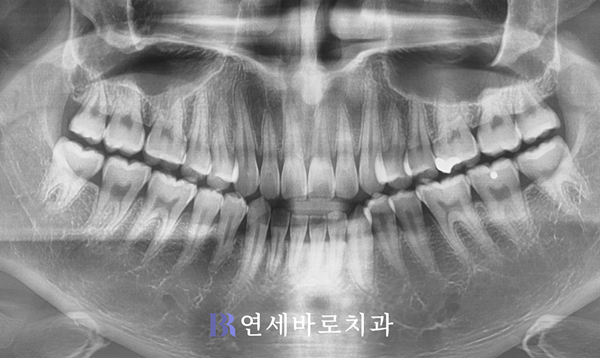

치아는 오히려 건강했습니다.

치열도 가지런한 편이었구요.

총생도 그리 많지 않았습니다.

문제는 바로 턱의 크기였습니다.

상악과 하악이 잘 맞지 않아서

상하교합에 문제를 일으켰습니다.

앞니의 끝부분이 서로 맞닿은

절단교합이 관찰되었습니다.

그러면서 아랫니가 한쪽으로

치우친 모습을 보였습니다.

이로 인해 중심선이 틀어져

불일치하게 되어버렸습니다.

장기적으로 방치할 경우,

전치부의 길이가 점차

짧아질 것이 우려됐습니다.